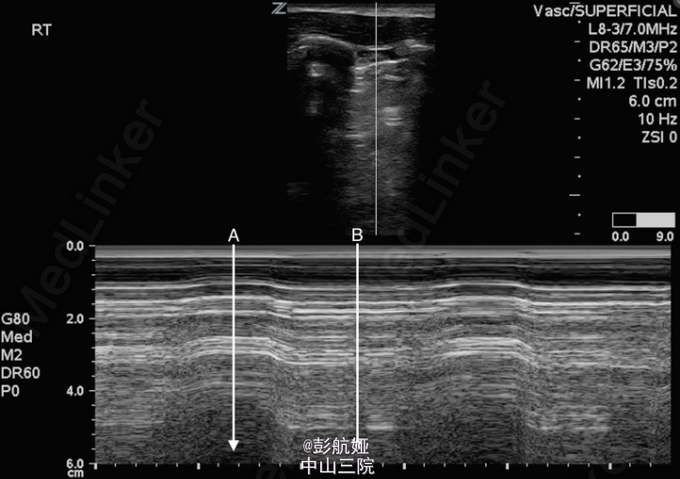

查体:体温:37℃,脉搏:99次/分,呼吸:32次/分,血压:130/84mmHg,鼻导管吸氧流量4L/min时,血氧饱和度:94%,双上肺呼吸音粗,双下肺呼吸音减弱。胸部拍片提示:右侧肺部肺大疱,正常肺组织完全被压缩,并合并气胸可能性大,患者无法平卧行CT检查,床边B超提示:右侧肺部未见滑行线,需与气胸、肺气肿及肺炎相鉴别。

鉴别肺大疱与气胸是十分重要的,肺大疱的患者气胸风险增加,普通胸片检查没有CT敏感,但患者病情通常无法平稳至可行CT检查;肺部的超声检查此时可作为一项可靠地诊断方法,肺部滑行线的出现可以排除气胸,而肺点出现时就可以考虑合并气胸。